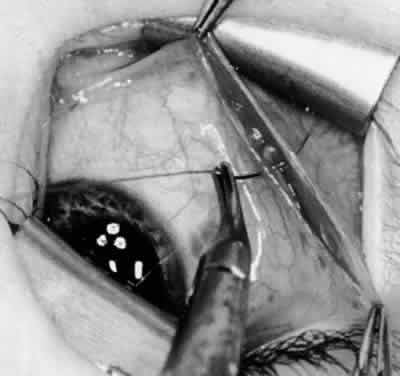

Fig. 21. A hemostat is placed adjacent to the insertion of the right inferior oblique muscle.

Fig. 22. An Aebli scissor is used to section the inferior oblique muscle from the globe.

Fig. 23. The inferior oblique muscle is drawn into the operative field with a hemostat. This step may be used for the recession procedure if the surgeon is concerned about the placement of the 6-0 Vicryl suture while the muscle is attached to the globe in the proximity of the macula. The recession sequence would follow after the placement of the suture while the muscle is grasped in the hemostat.

Fig. 24. The eyelid speculum is removed and a Desmarres lid retractor is placed inferiorly. The inferior oblique muscle is drawn superiorly and nasally. The fusiform expansion of the inferior oblique muscle is evident on the posterior border, where the nerve to the inferior oblique muscle and artery and vein enter the inferior oblique muscle. The Stevens muscle hook is used to hook the neurovascular bundle.

Fig. 25. The hook is advanced further for identification of the neurovascular bundle on the inferior oblique muscle.

Fig. 26. Cautery is applied to sever the neurovascular bundle, and a sponge is used to protect the sclera and lids from cautery.

Fig. 27. As the neurovascular bundle is severed completely, the inferior oblique muscle will be released of the normal tension provided by the neurovascular bundle on the posterior border of the inferior oblique muscle.

Fig. 28. The inferior oblique muscle is drawn further into the operative field, and a 3-0 Vicryl suture ligature is applied about the belly of the muscle.

Fig. 29. Cautery is used to sever the inferior oblique muscle and to provide hemostasis.

Fig. 30. The stump of muscle is placed through the Tenon's capsule opening. The surgeon must apply sufficient cautery to prevent postoperative bleeding.

Fig. 31. The inferior oblique muscle stump is visible at the opening in the Tenon's capsule before closure with 6-0 or 7-0 Vicryl suture. The S-28 half-circle curved needle is preferred to the S-29 needle, which has a 3–8-circle curve.

Fig. 32. The Tenon's capsule opening is closed with 6-0 or 7-0 Vicryl suture to place the inferior oblique muscle entirely outside Tenon's capsule.